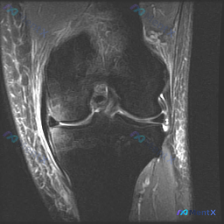

今天遇到一个挺有代表性的病例,主诉提示膝关节半月板异常,只提供了单张膝盖MRI冠状位T1加权像,整理一下分析思路跟大家分享。 一、病例核心信息 核心问题:患者主诉提示半月板异常,仅提供单一层面冠状位T1加权MRI读片 影像观察结果: 1. 骨骼:股骨远端、胫骨近端骨皮质完整连续,骨髓腔T1信号为均匀...

看到这张膝关节MRI的读片请求,目标是找半月板异常,但整理完全片发现这个病例的陷阱挺典型,分享出来给大家参考。 一、病例影像基本信息 这是一张膝关节冠状位T1加权磁共振图像,只有单一层面单序列,我们先按结构捋一遍所见: 1. 骨骼结构:股骨远端、胫骨近端骨皮质连续,没有明显骨折线;但整个骨髓腔在T1...

看到这个病例挺有代表性的:临床怀疑半月板异常,但提供的只有单张膝关节MRI冠状位T1加权序列,读片下来居然没发现明确异常,整理一下我的分析思路给大家参考。 先整理病例影像核心信息 这是膝关节MRI冠状位T1加权序列,我们先明确序列特点:T1加权主要看解剖结构,脂肪/骨髓是高/中高信号,液体、皮质骨、...